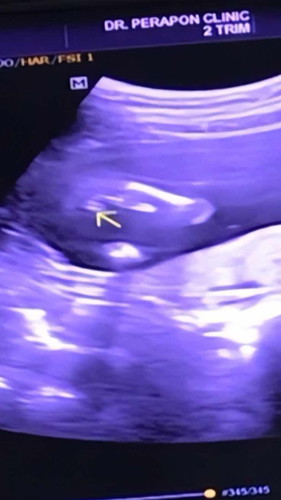

สอบถามหน่อยค่า

น้องเป็นผู้หญิงหรือผู้ชายคะแม่ๆ

ลูกชายค่ะ